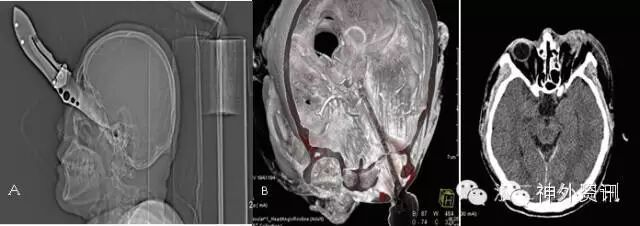

图11. 钢钎经口咽入颅,成功拔除(有点类似于本病例,患者,男,44岁)。

图12. 刀片插入眶颅,顺利拔除(患者,女,67岁)。